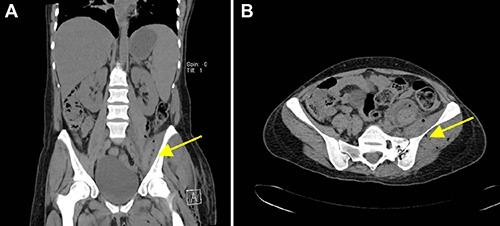

Necrotizing soft tissue infection of an extremity is a rare but life-threatening disease. The disease is an infection that involves the soft tissue layer and is characterized by rapidly spreading inflammation (especially of the fascial planes and the surrounding tissues) with a high mortality. Early diagnosis is essential for the outcome of the patients. Radical surgical debridement is the treatment of choice. The predisposing factors are immunosuppression, diabetes mellitus and drug abuse. This report presents a case of necrotizing fasciitis in the thigh, following an abscess of the sacro-iliac joint, as a rare complication in a young, immunosuppressed woman. The patient's history revealed intravenous drug abuse and hepatitis C. After immediate diagnosis by magnetic resonance imaging, radical surgical debridement was required and performed. Prior to soft tissue coverage with a split skin graft, five additional sequential debridements were necessary. During her hospital stay, the patient experienced further cerebral and pulmonary septic embolisms and an infection of the elbow. Six months after admission, the patient was discharged in good condition to a rehabilitation center. Necrotizing fasciitis is a life-threatening complication following an abscess of the sacro-iliac joint. Physicians must be vigilant to inflammatory signs and pain in immunosuppressed patients. An abscess of the sacro-iliac joint is rare, but complications of an untreated abscess can be fatal in these patients.